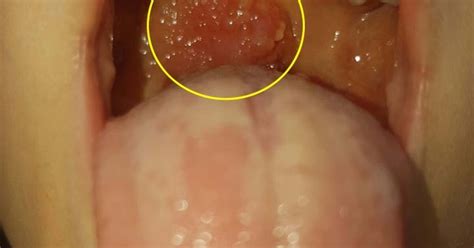

Oropharyngeal Cancer - Throat Cancer Pictures | Kimaja ... from i0.wp.com Diseases like laryngeal cancer, acid reflux and other inflammatory processes of the larynx, as a result, can cause ear pain. It is about 5 cm long and is sometimes called the voice box. Each year, approximately 13,000 people in the u.s. Many types of throat cancer. Throat cancer is a type of head and neck cancer that occurs in the pharynx or the larynx. Feeling like you need to. Cancer of the larynx is often grouped into early (stage i), intermediate (stage ii) or advanced (stages iii & iv) disease groups. What does a throat cancer lump feel like?

Common symptoms of laryngeal cancers include coughing, voice changes, hoarseness and difficulty swallowing. Laryngeal cancer affects the larynx, or voice box. Many types of throat cancer. Laryngoscopy is a procedure a doctor uses to look at the larynx (voice box), including the vocal cords, as well as nearby structures like the back of the throat. Throat cancer is a condition that is characterized by the development of malignant tumors in the throat (pharynx), voice box (larynx) or tonsils. Is the lump painful at all times, or just when swallowing? Cancer can cause almost any type of sign or symptom. Laryngeal cancer symptoms include voice changes, such as hoarseness, and a sore throat or cough that doesn't go away. Please help, i am terrified! I am a 19 year old male. What does a throat cancer lump feel like? This is known as the adam's apple. Tongue cancer develops at the.